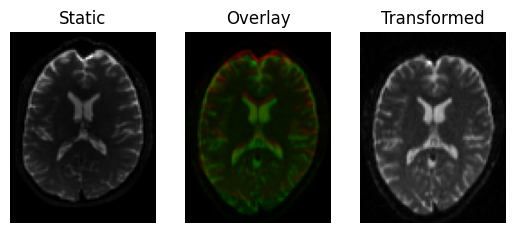

Finally, let’s refine with a full affine transform (translation, rotation, scale and shear), it is safer to fit more degrees of freedom now since we must be very close to the optimal transform

This results in a slight shear and scale

transformed = affine.transform(moving)

<Figure size 640x480 with 3 Axes>

Registration result with an affine transform, using Mutual Information.